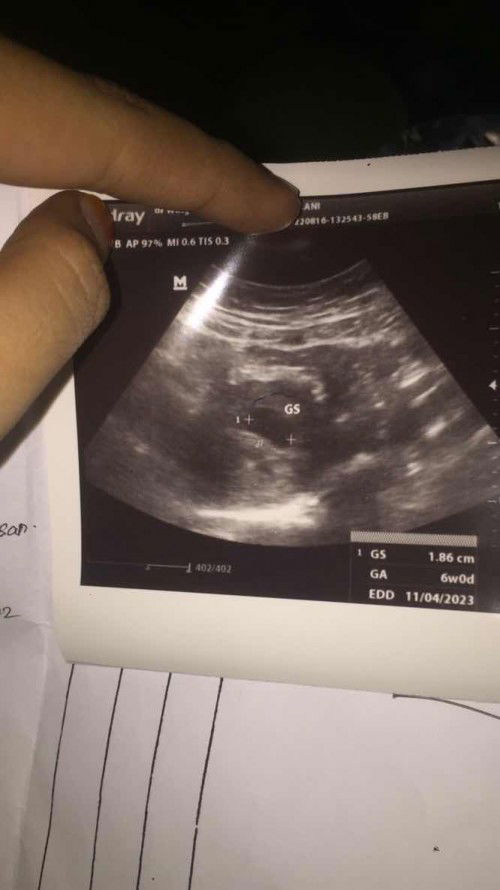

sama bun saya hamil pertama usg 6w baru keelihatn kantongnya ,dann sama dokternya di kasih vitamin sama penguat kandungam,satu mingggu lagi di suruh balikk ,dan pas usg lagi udah kelihatann tapi masih kecil banget ,detak jantungnya pun udah adaa ,skrng usia kehamilan 8w

aku juga waktu 6 week baru keliatan kantongnya bun, pas 8 week Alhamdulillah udah keliatan janin dan detak jantungnya. semangat ya bun semoga sehat terus

setiap orng beda2 bun, kmrn wkt aku usg 6w5d sudh keliatan janin dan detak jantung, coba usg 2 mggu lg .. smgat bun

sama bund waktu kemaren aku usg 6minggu baru ada kantung rahim nya aja, semangat ya bumil bumil happy selalu🥰

aku waktu usg UK 6week 2 hari udah ada detak jantung nya, tapi pas itu aku usg transvaginal